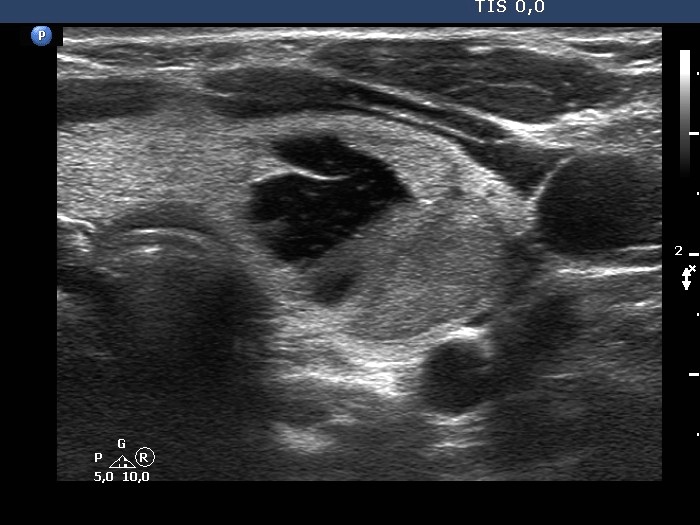

Examination one year later (ultrasonographic picture 2)

Left lobe, another transverse scan. The dorsal part of the solid area is minimally hypoechogenic.